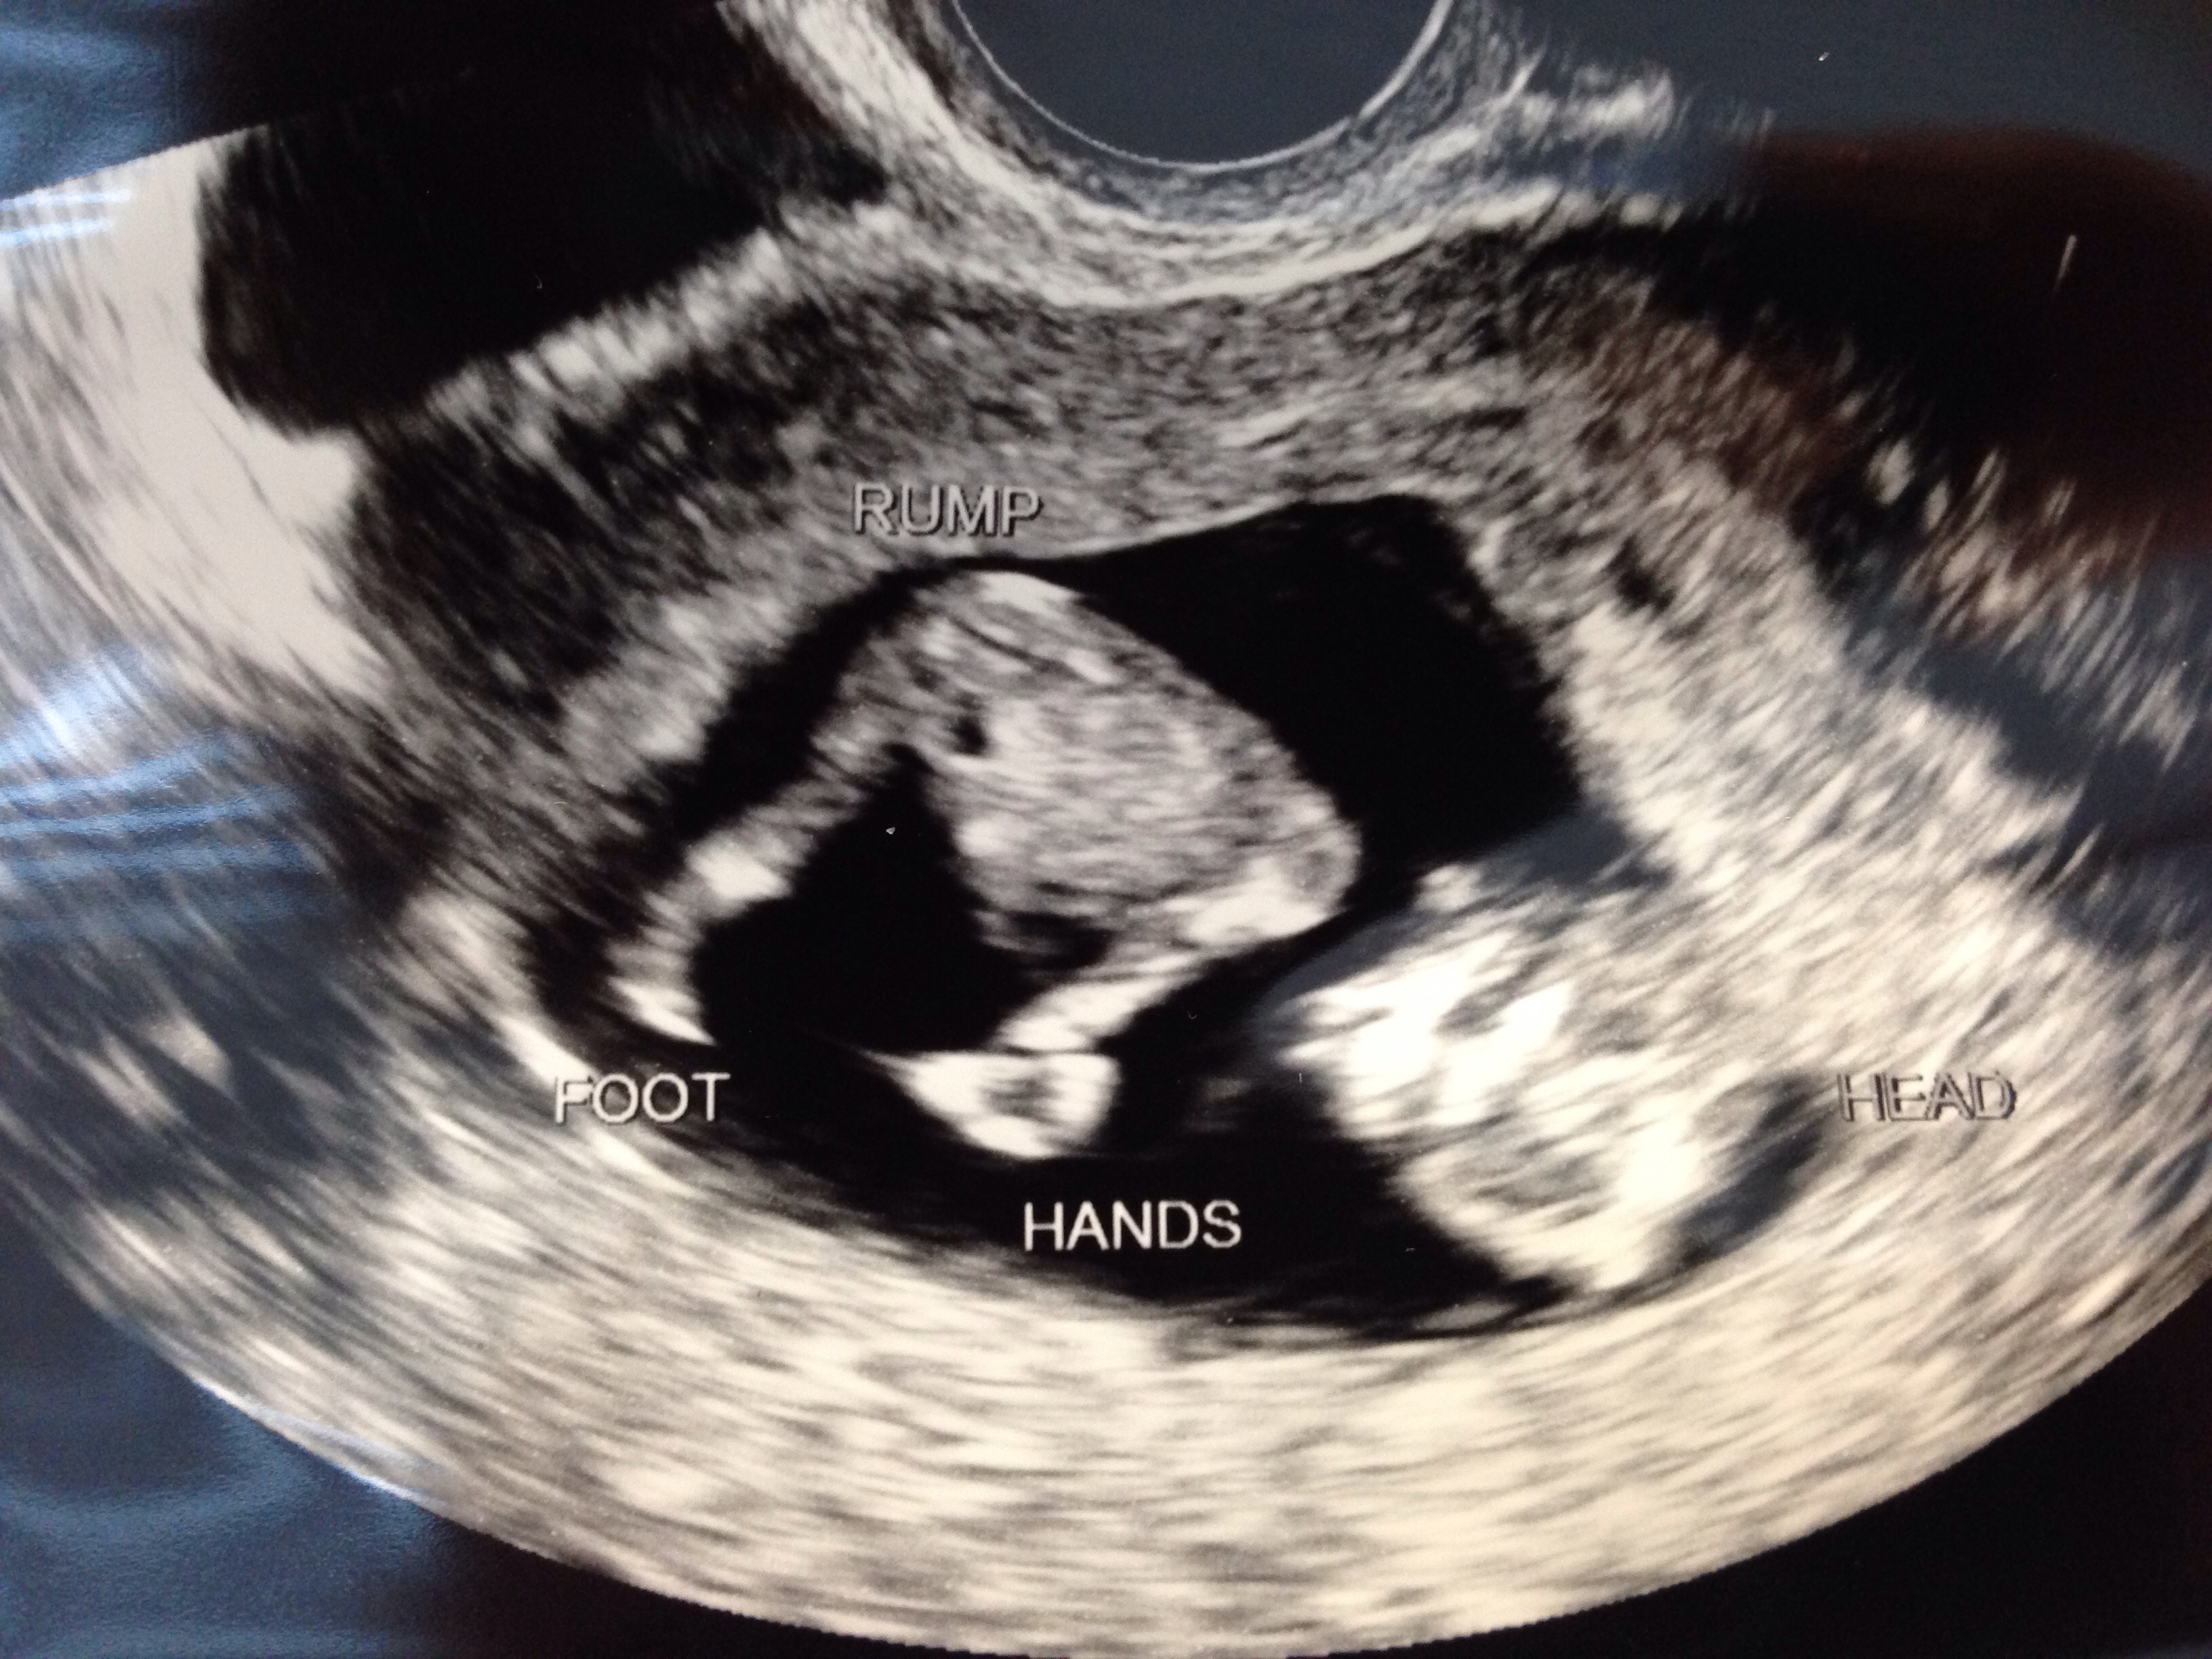

10/17: U/S shows healthy bean @ 6w6d, HR 119 10/25: U/S shows bean is growing @ 8w0d, HR 158!

@allytales - there's totally a baby in there!!!